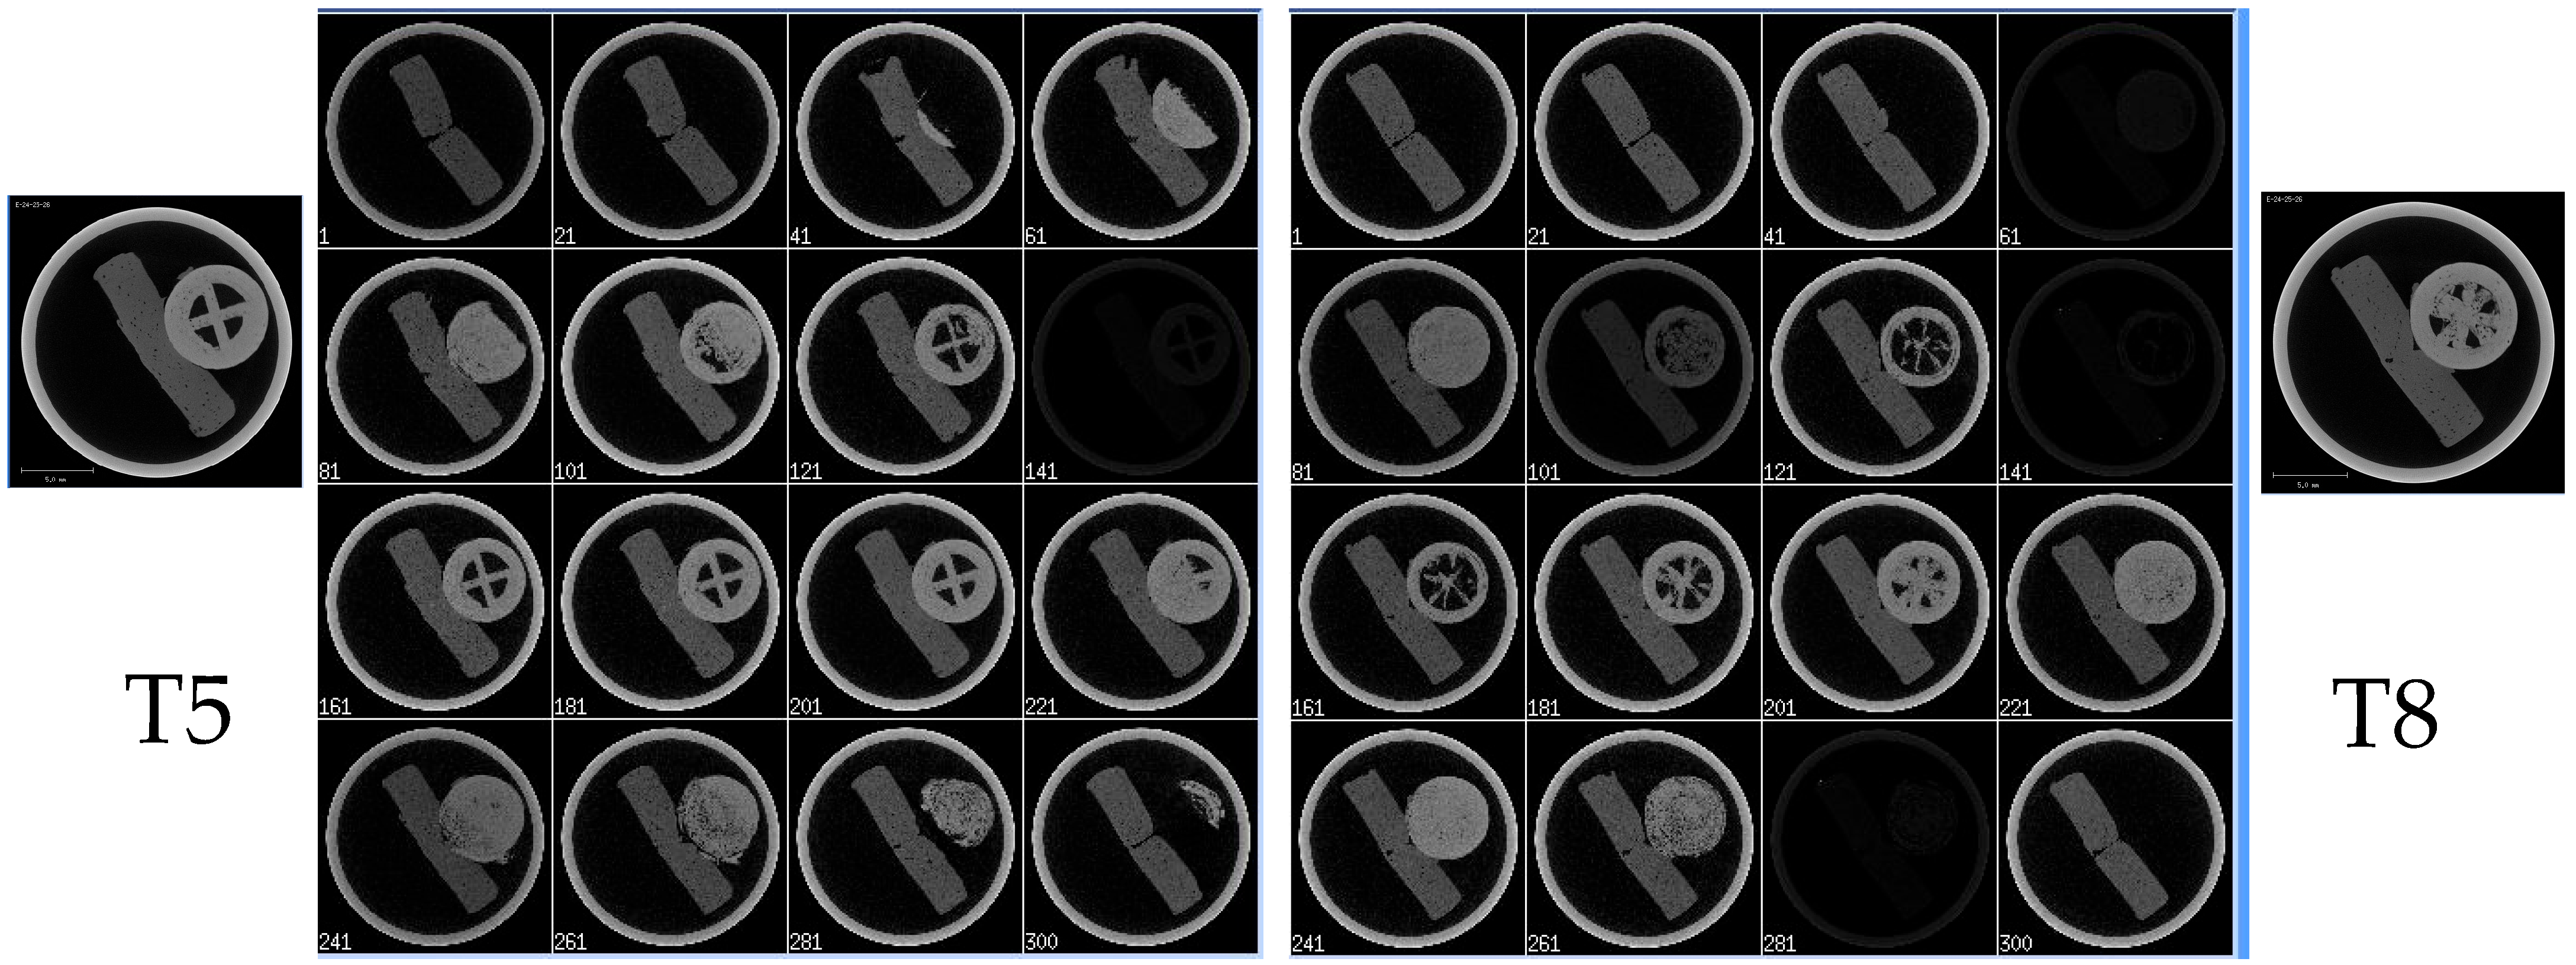

3.13. Micro-CT

| T5 | No air pocket | One wall | 5 | 25 | 30 | 180 | 0.2 | 100 | Kollicoat® IR |

| T8 | No air pocket | One wall | 5 | 50 | 30 | 180 | 0.2 | 100 | Kollicoat® IR |